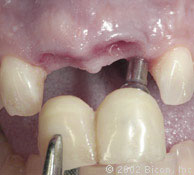

Вид после установки

Установка двух 5.0mm x 4.0mm Stealth Shouldered Abutment